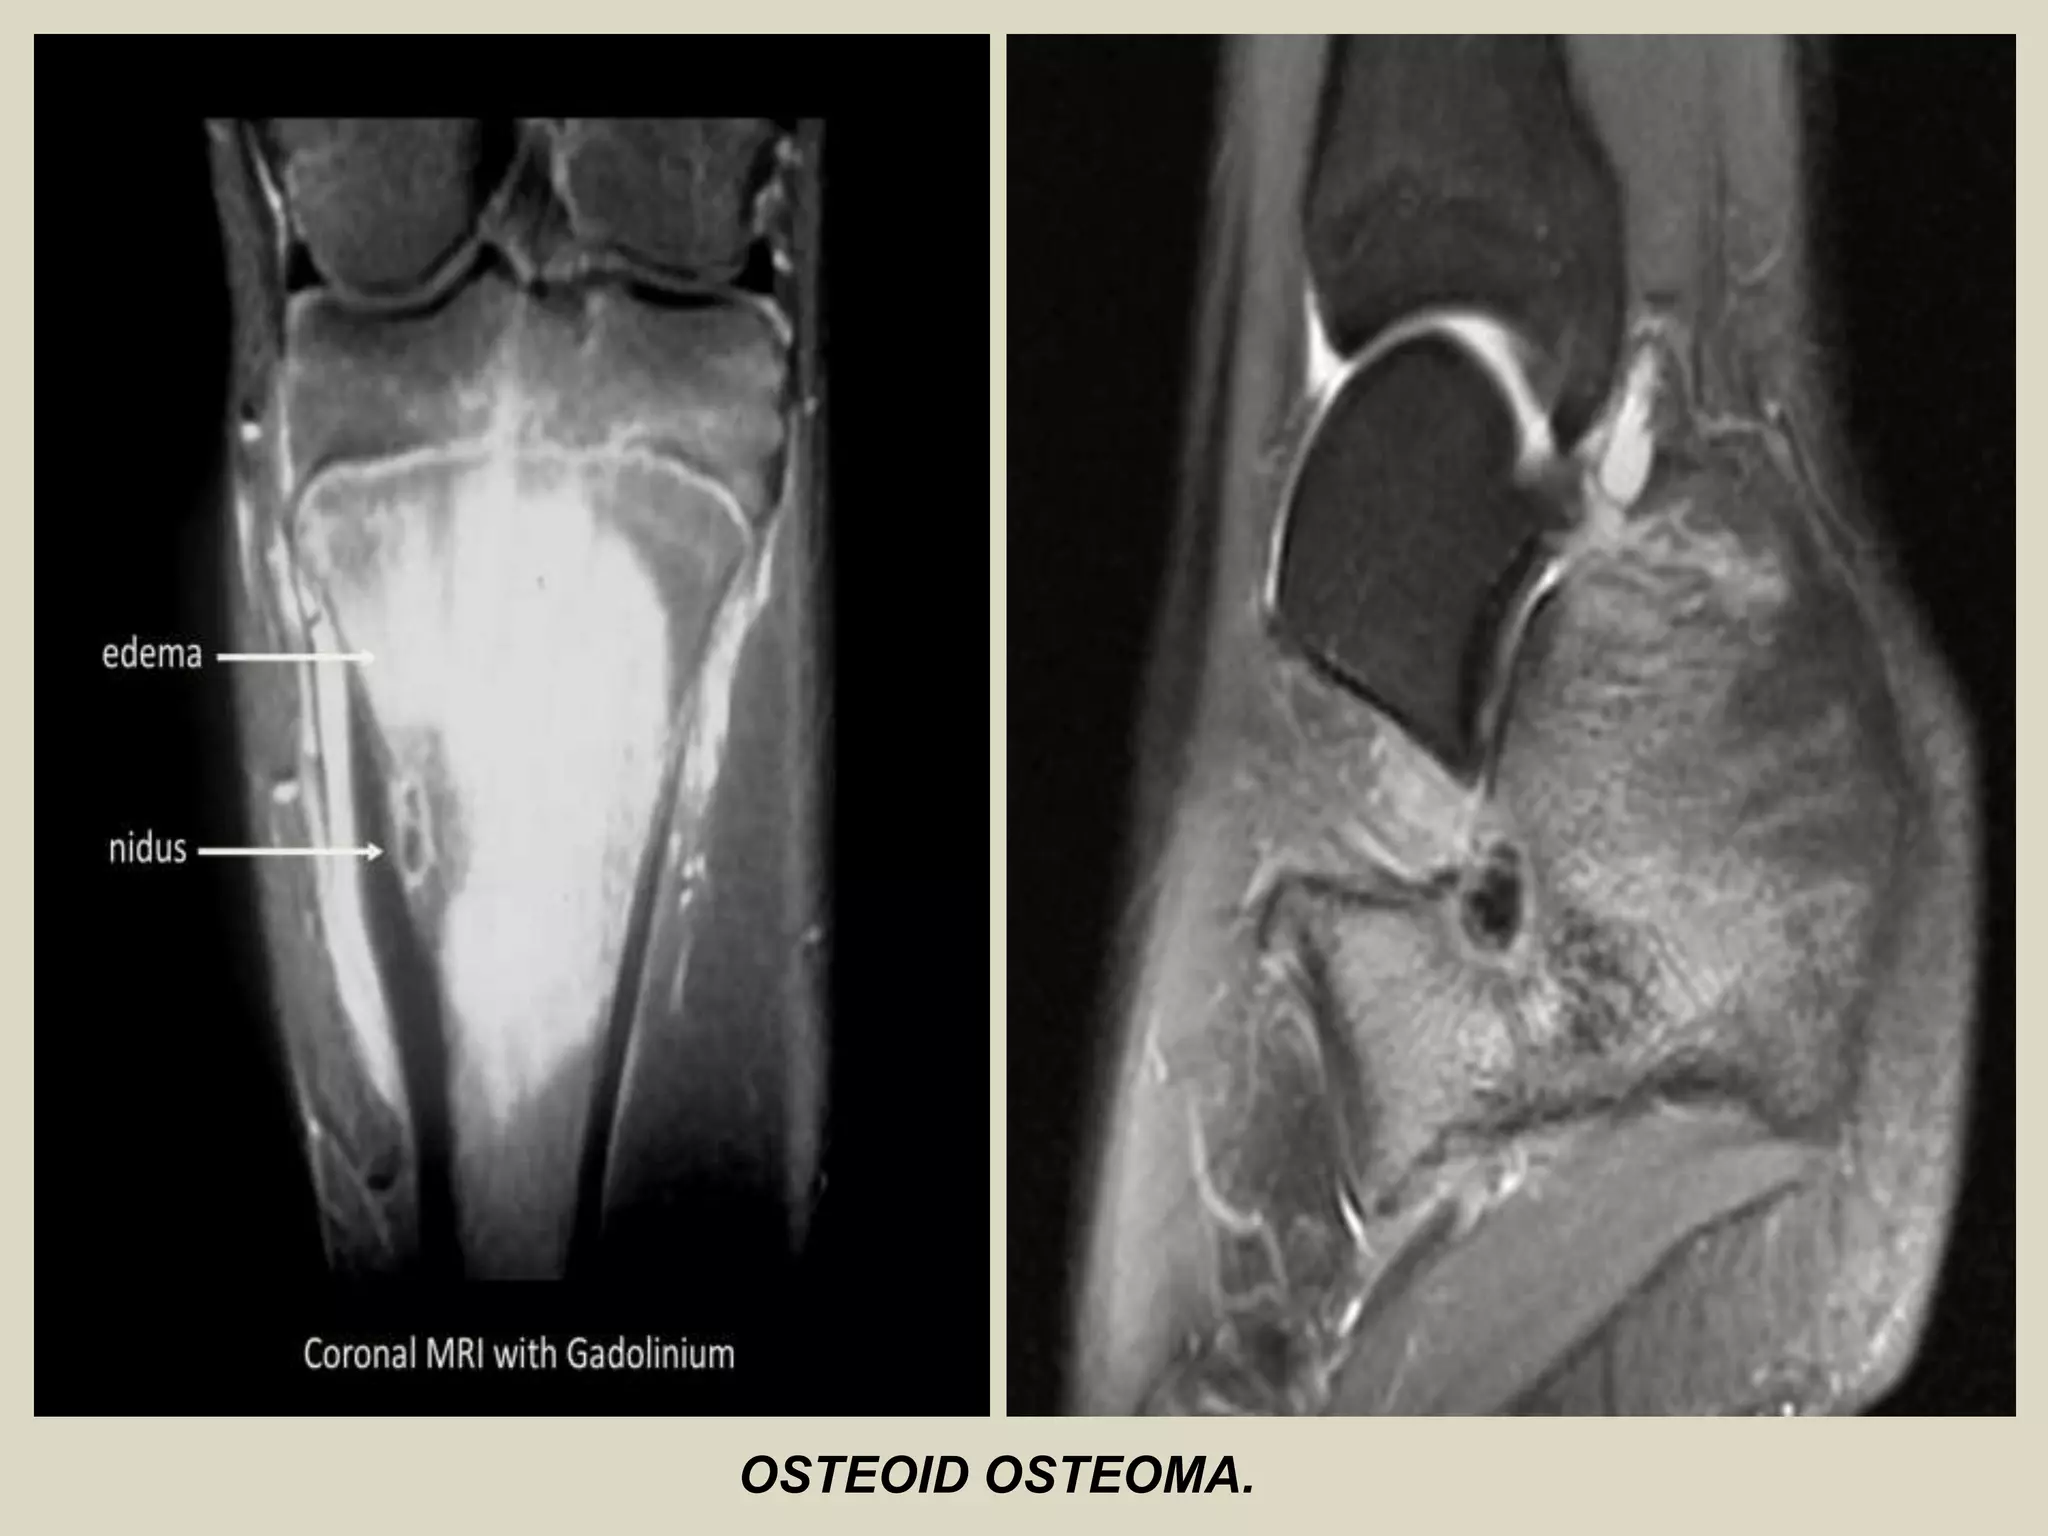

OSTEOID OSTEOMA

- Benign bone-forming tumor.

- Similar to osteoblastoma but smaller size (1.5 - 2.0 cm).

- Children and adolescent.

- Most common in long bones, femur/tibia (cortex of

metaphysis)

- May be found in any bone.

- Intense localized pain particularly at night.

- Pain relieved by aspirin, NSAIDs or surgery.

- Small, round lucency.

- Variable mineralization surrounded by extensive sclerosis.

OSTEOID OSTEOMA.